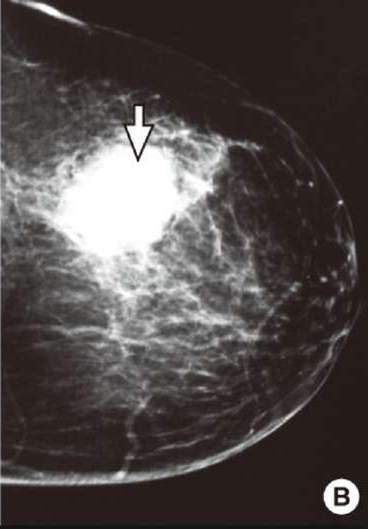

breast cancer mammogram is in which plane?

1- medial lateral oblique MLO ( pectoralis muscle and axillary vessels)

2- cranio-caudal

medial lateral oblique MLO

CC

craniocaudal

The typical high-risk finding will be a speculated mass with abnormal architecture & asymmetry, with clustered micro- calcification

breast cancer means:

irregular margin

speculated mass